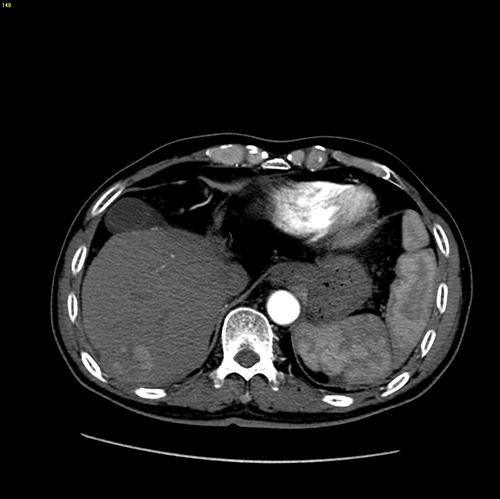

S7肝癌 门脉高压脾亢---S7切除 贲门周围血管离断